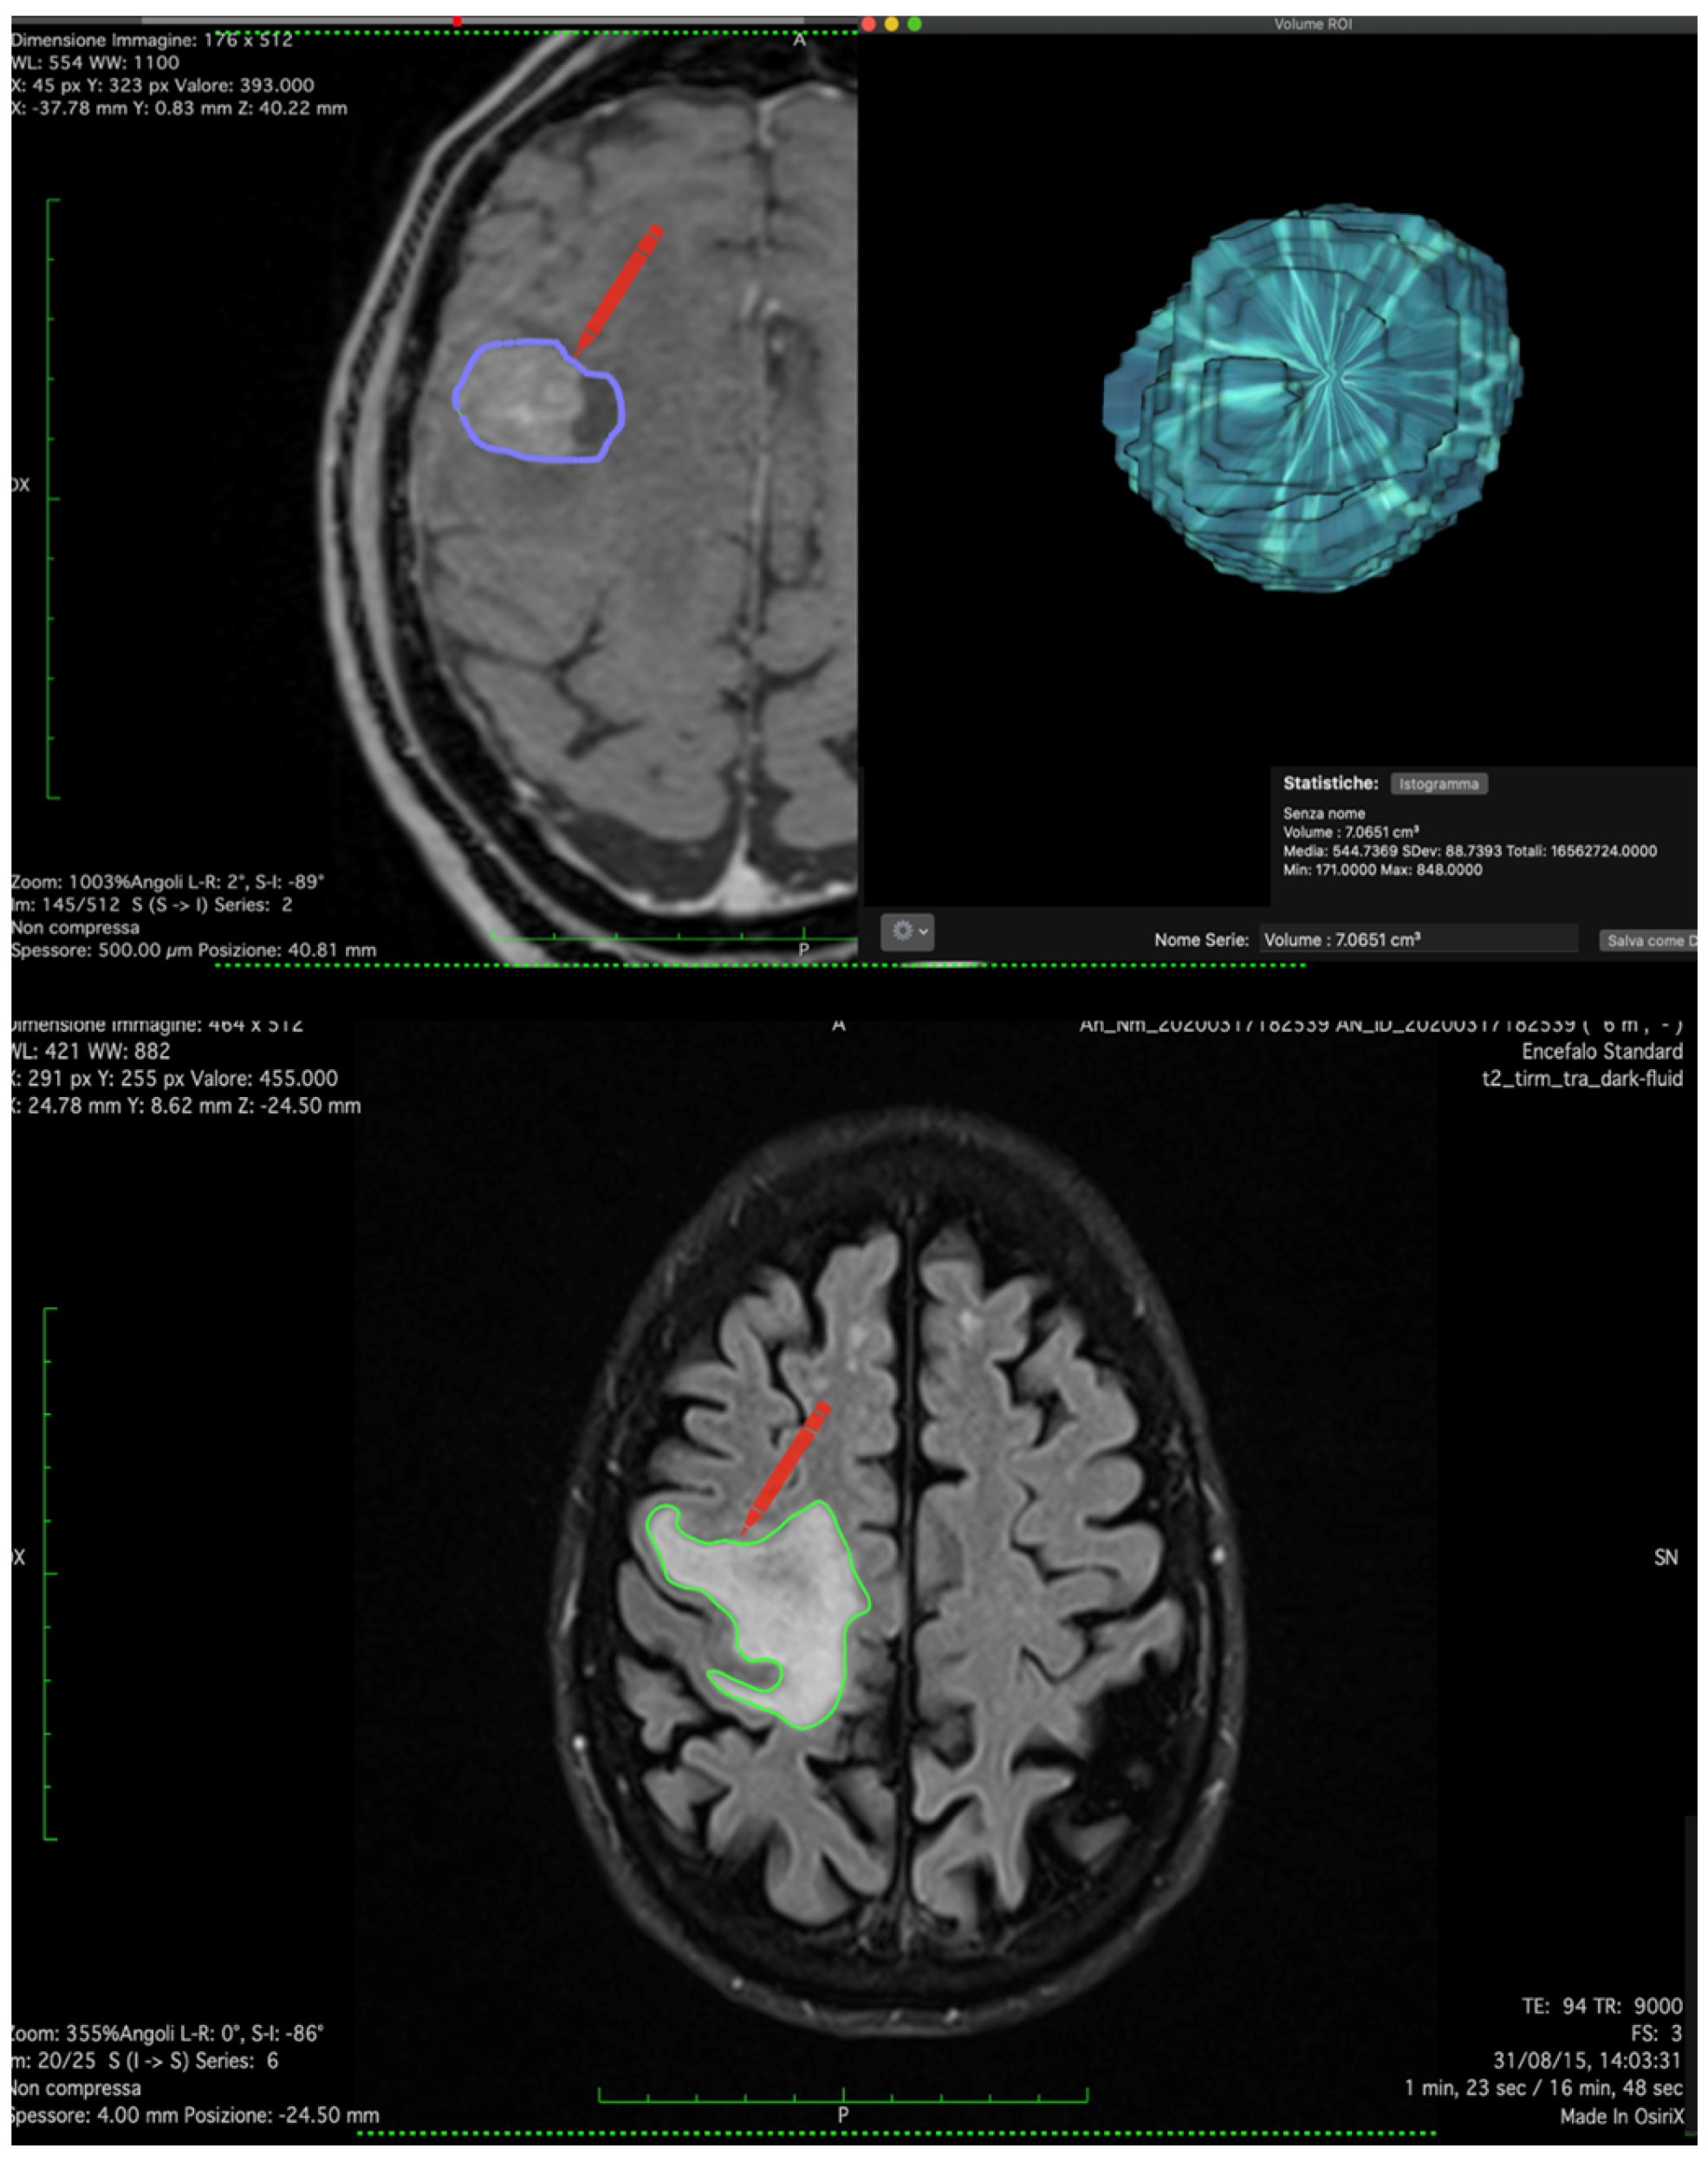

- Paglia, F.; Caporlingua, A.; Armocida, D.; Rizzo, F.; Santoro, A.; D’angelo, L. Preoperative 3D volume reconstruction of the posterior wall of the sphenoid sinus with Horos: A free, simple and reliable tool in endoscopic endonasal trans-sphenoidal surgery. Neurocirugia 2022, 33, 219–226. [Google Scholar] [CrossRef]

| Volume (cm3) | 14.62 ± 18.5 |

| Edema Volume (cm3) | 54.21 ± 45.76 |

| Volume (cm3) | 22.38 ± 21.35 | 7.68 ± 6.44 | 0.046 |

| Edema volume (cm3) | 72.44 ± 60.71 | 31.92 | 0.028 |